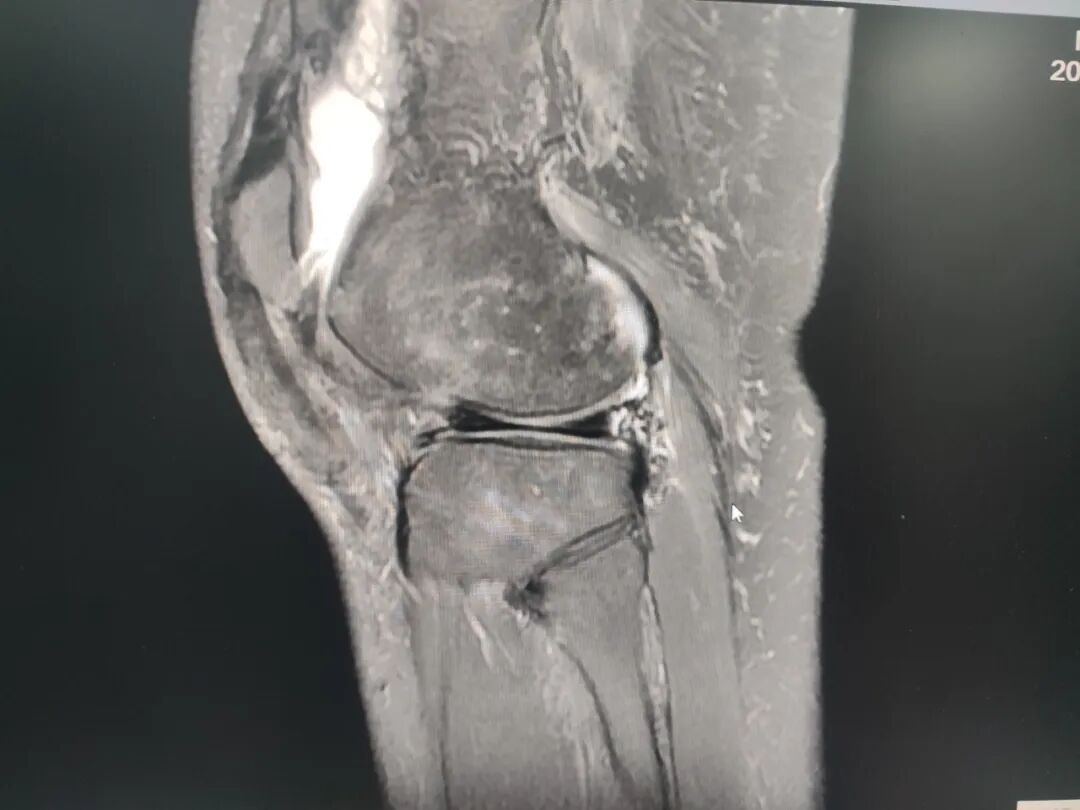

关节疼痛难忍?放疗精准“灭火”

精准,是治疗的关键